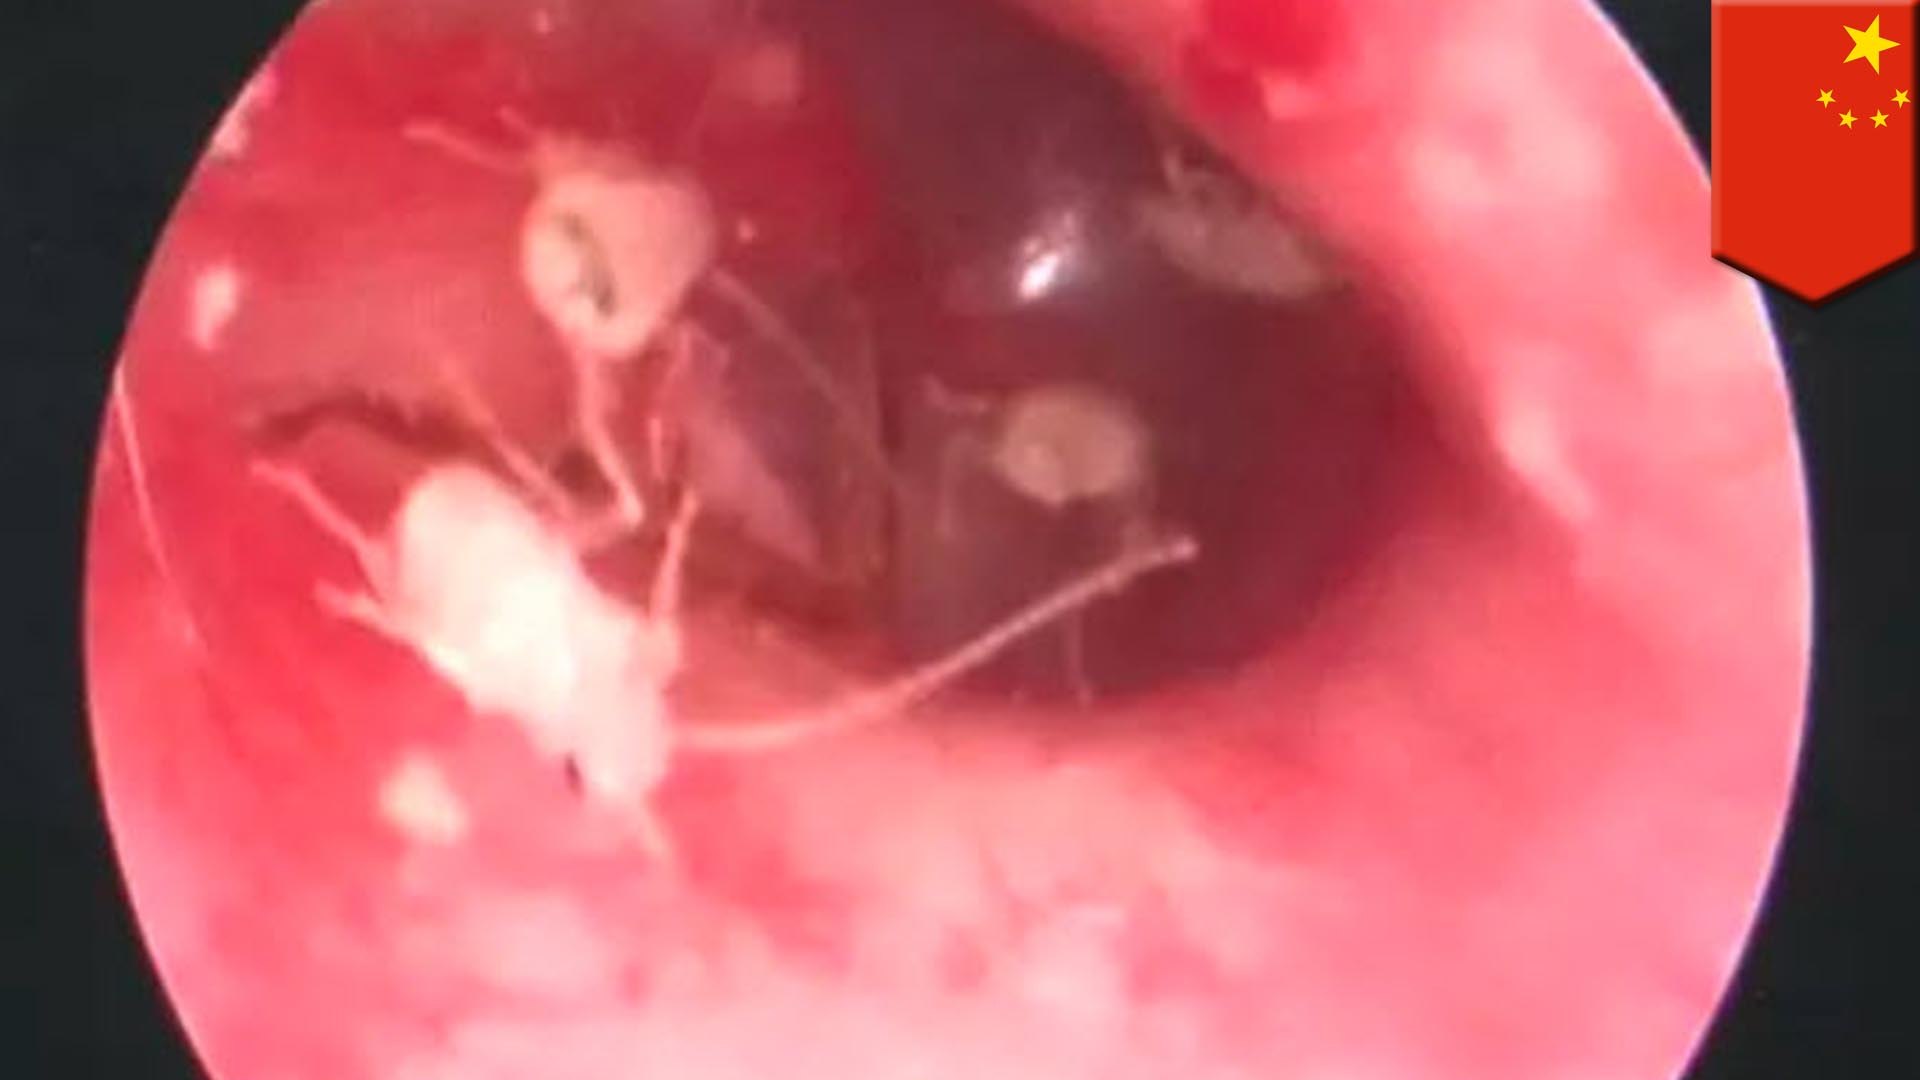

耳の中にゴキブリ 動画-繁殖しているのは家の中だけだと思っていませんか。実は車の中はゴキブリにとって、格好の棲み処だということをご存じでしたか。 車内にゴキブリが入ってくるのは何で? ゴキブリの侵入経路、それは車体にある小さな隙間です。 成虫なら5㎜、幼虫なら05㎜の隙間があればok 家もそうです耳の中の音と痒みに耐えられなくなった男がとった行動とは? (マンガ動画) 漫画ゴキブリが耳の中で25匹もの子を産み育てていた

ゴキブリが耳の中で産卵し26匹を摘出 中国にいる 害虫の生命力 がハンパない 日刊spa

男性の耳に入った母ゴキブリ 10匹以上の子供を産んで家族で耳暮らし 中国 ゴキブリ出演中 19年11月15日 エキサイトニュース

激痛を感じた中国人男性 耳の中にゴキブリ家族が住みついていた Vaience

中国人男性の耳に棲みついたゴキブリ 耳の中で卵が孵化して合計26匹を摘出 エニグム Enigme

ゴキブリが男性の耳に入り産卵 25匹孵化 イヤー 耳だけにイヤー 魔空間にゅーす

漫画 ゴキブリが耳の中で25匹もの子を産み育てていた 耳の中の音と痒みに耐えられなくなった男がとった行動とは マンガ動画 Youtube

ゴキブリが男性の耳に卵を産み付ける衝撃の事態が発生 Gigazine